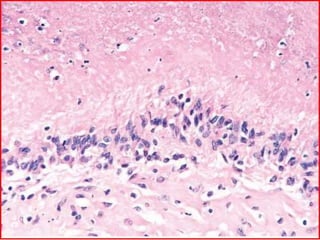

 Rheumatoid subcutaneous nodules develop in about

one-fourth of patients, occurring along the extensor

surface of the forearm or other areas subjected to

mechanical pressure; rarely they can form in the lungs,

spleen, heart, aorta, and other viscera.

 Rheumatoid nodules are firm, nontender, oval or rounded

masses as large as 2 cm in diameter.

 Microscopically, they are characterized by a central focus of

fibrinoid necrosis surrounded by a palisade of

macrophages, which in turn is rimmed by granulation

tissue

• 35.

 Rheumatoid subcutaneousnodules develop in about one-fourth of patients, occurring along the extensor surface of the forearm or other areas subjected to mechanical pressure; rarely they can form in the lungs, spleen, heart, aorta, and other viscera.  Rheumatoid nodules are firm, nontender, oval or rounded masses as large as 2 cm in diameter.  Microscopically, they are characterized by a central focus of fibrinoid necrosis surrounded by a palisade of macrophages, which in turn is rimmed by granulation tissue